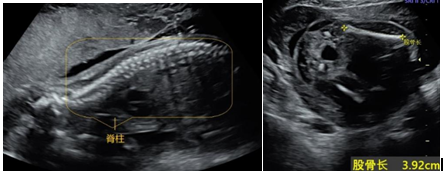

孕20-26周TA已经长得有模有样,系统结构清晰,头身大小合适,明显长壮实了。超声检查时会看到你的宝贝在羊水里自“游”自在,或打个哈欠,或伸伸懒腰,或翻身躲藏,或手舞足蹈。孕20-26周是超声检查胎儿解剖结构和筛查胎儿畸形(大排畸)最适宜的时间,可以见证TA的颅脑结构、颜面部、颈部、肺、心脏、肝胆、胃肠、肾脏、膀胱、脊柱、四肢等结构(图片6-1、图6-2)。胎儿这些系统和器官结构的检查,是超声医生通过慧眼观察和巧手找寻,最终在上百个超声切面上实现的。上述检查为我们提供了如此美妙的胎儿图像,同时保障了优生优育,不禁感慨小小超声大大能量!

图6-1 超声显示:中孕